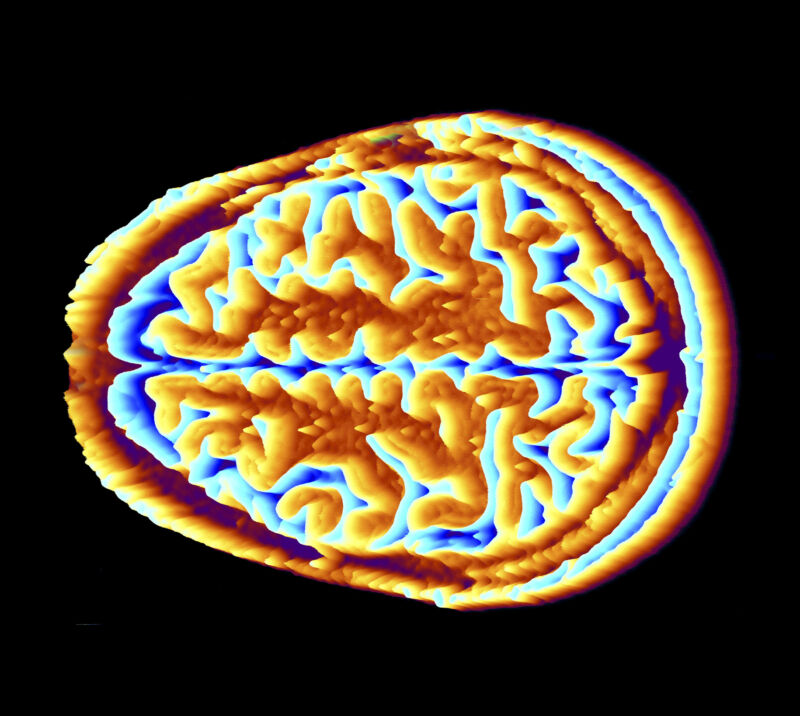

Colored image of a cross section of the skull and brain.

Enlarge (credit: Getty Images)